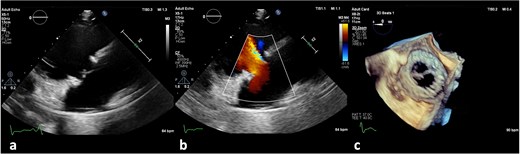

On the third day of hospitalization, transesophageal echocardiography revealed only moderate mitral regurgitation (Videos 3 and 4). However, on day 11, follow-up echocardiography showed a 7 × 18 mm vegetation on the prosthetic aortic valve, with a 5 × 7 mm floating formation (Fig. 2, Videos 5 and 6). By day 21, the vegetation had progressed, with a new formation on the tricuspid valve, an aortic annulus abscess, and worsened mitral regurgitation to severe (Figs 1 and 3, Videos 7 and 8). The development of double-sided endocarditis is very rare, and since the patient experienced it twice, congenital predisposing factors such as Patent Foramen Ovale and ventricular septal defects were ruled out. It was hypothesized that multiple predisposing factors ultimately led to the reinfection. Active IV drug use and its potential immunosuppressive effects, along with persistent poor dental condition and recurrent cutaneous infections, were identified as the main contributors, in addition to the patient’s overall non-adherence, for the development of double-sided endocarditis on two occasions.

Antero-septal paravalvular leak (PVL) of the prosthetic aortic valve in TTE (a) TTE PLAX (b), PSAX (c) 5CV (day 21 of hospitalization).